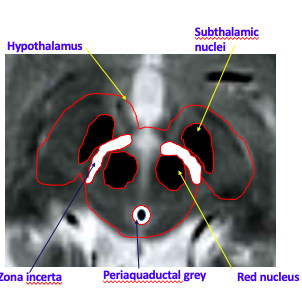

Brain regions for DBS

Which areas of the brain targeted for tremor? [3]

Which areas of the brain targeted for Dystonia? [1]

A

Tremor:

* Zona incerta

* Subthalamic nucleus

* GPin

Dystonia:

Which structures are the arrows pointing to? [5]